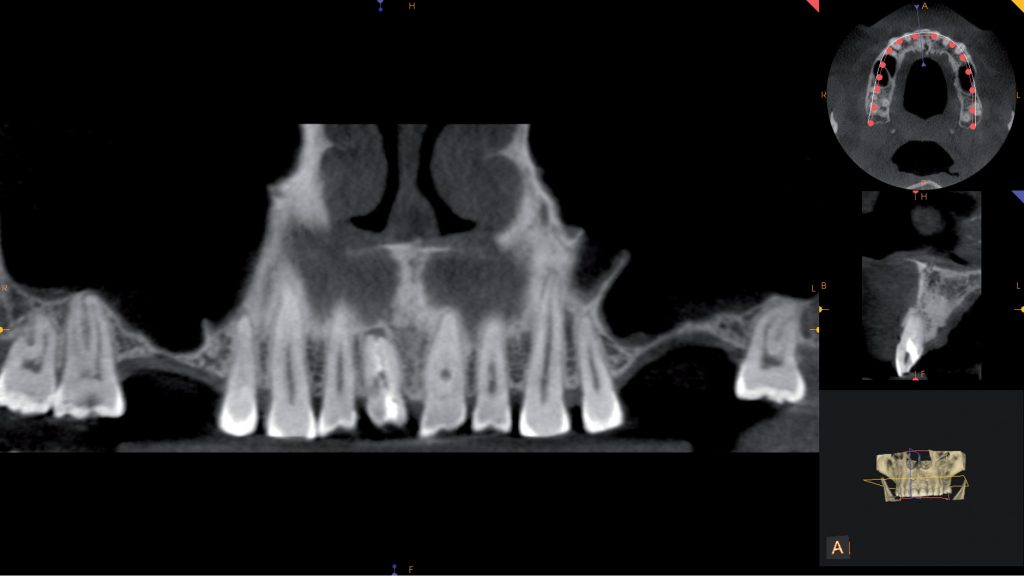

Streszczenie: Zewnętrzna resorpcja przyszyjkowa jest odmianą zewnętrznej resorpcji korzenia. Jej cechami charakterystycznymi są położenie w obszarze przyszyjkowym oraz infiltracyjny wzrost. W artykule przedstawiono korzyści z zastosowania badania CBCT w diagnostyce i planowaniu leczenia zewnętrznej resorpcjii przyszyjkowej. Opisany przypadek prezentuje postępowanie zachowawczo-chirurgiczne u pacjenta z zewnętrzną resorpcją przyszyjkową w zębie 11.

Summary: External resorption is a variation of the external cervical stage of root resorption. Its characteristic feature is its location in the cervical area and increase infiltration. The article presents the benefits of using CBCT examination in the diagnosis and treatment planning of external cervical resorption. This case presents a conservative surgical procedure in a patient with external cervical resorption in the tooth 11.